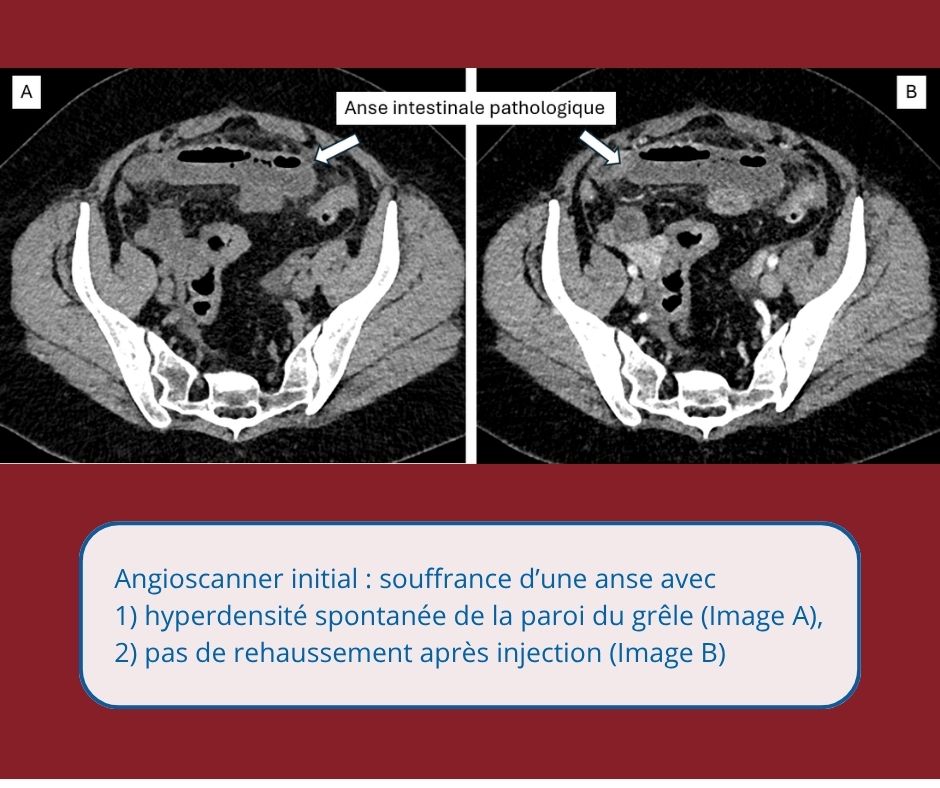

Episode 1 – Une ischémie veineuse compliquée